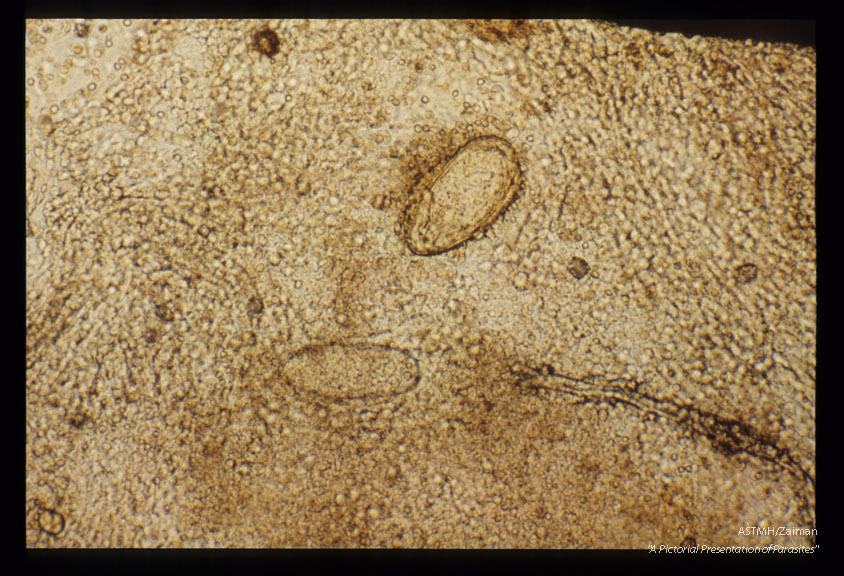

Bladder biopsies from a tourist from Illinois.

Schistosoma haematobium

Description: Bladder biopsies from a tourist from Illinois.